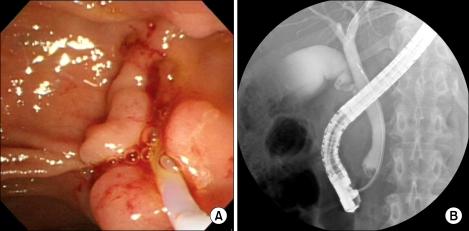

Robotic surgical system provides many unique advantages which might compensate the limitations of usual laparoscopic surgery. By using robotic surgical system, we performed robot-assisted laparoscopic pancreaticoduodenectomy (PD). A Sixty-two year old female patient with an ampullary mass underwent robot assisted PD due to imcomplete treatment of endoscopic ampullectomy. The removal of specimen and reconstruction were performed through small upper midline skin incision. Robot working time was about 8 hours, and blood loss was about 800 ml without blood transfusion. She returned to an oral diet on postoperative day 3. Grade B pancreatic leak was noted during the postoperative period, but was successfully managed by conservative management alone. We successfully performed da Vinci-assisted laparoscopic PD, and robot surgical system provided three-dimensional stable visualization and wrist-like motion of instrument facilitated complex operative procedures. More experiences are necessary to address real role of robot in far advanced laparoscopic pancreatic surgery.

https://cdn.ncbi.nlm.nih.gov/pmc/blobs/1d52/3229006/79e639bf6be7/jkss-81-355-g001.jpg